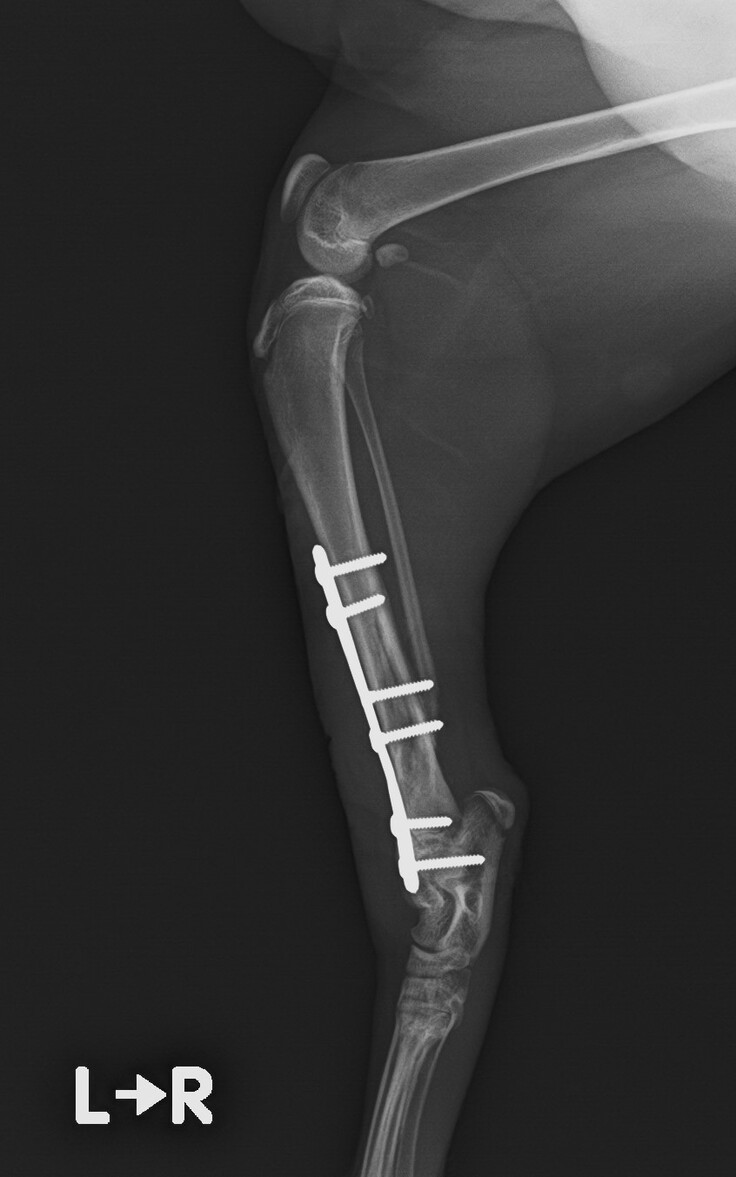

・右後ろ脚骨折

4月20日、右後ろ脚の骨折を治すため、プレートで固定する手術を行いました。

5月14日、抜糸と経過観察。まだプレートは入っていますが順調に回復しています。

7月初旬~中旬 プレート除去予定